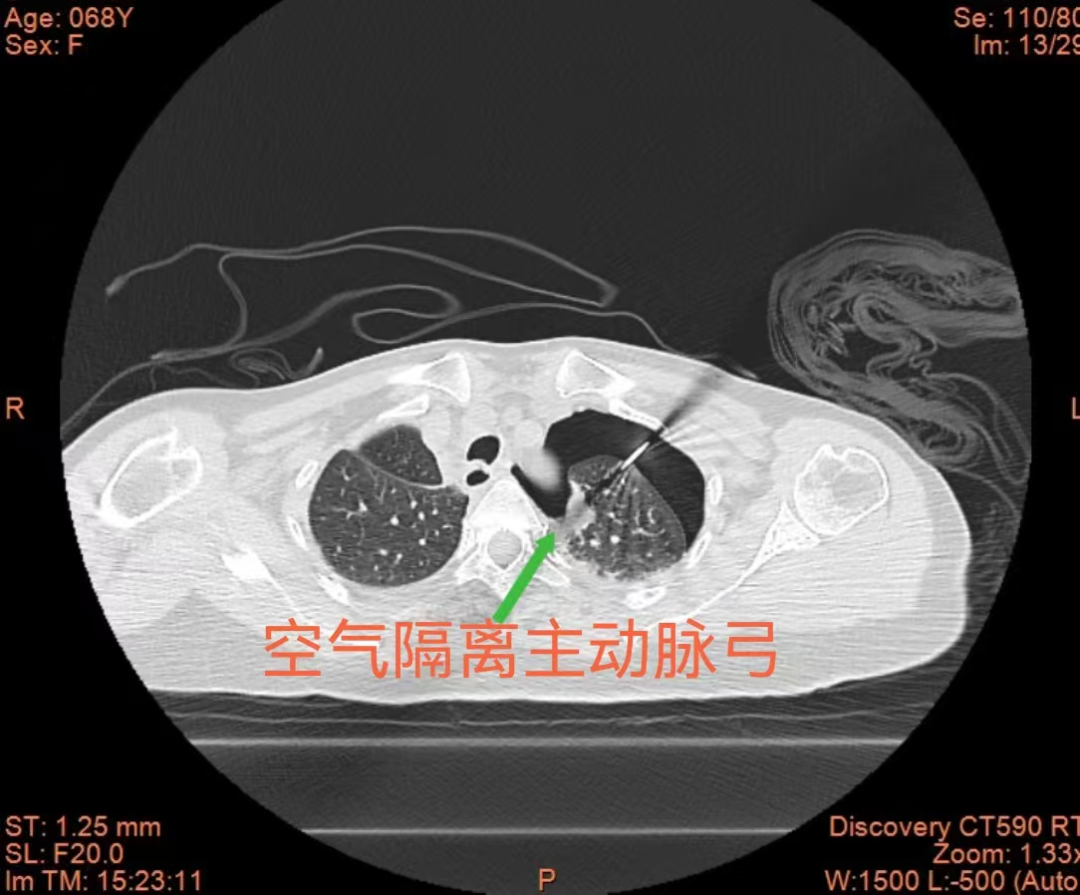

术中,团队在CT精准导航下,先向左侧胸腔缓慢注入空气,构建人工气胸,在左上肺结节与主动脉弓之间形成安全空气隔离带,同时配合液体隔离技术,有效减轻术中疼痛。凭借精准的穿刺技巧与术中的严密监测,消融针精准抵达病灶,手术顺利完成,目前患者已康复出院。